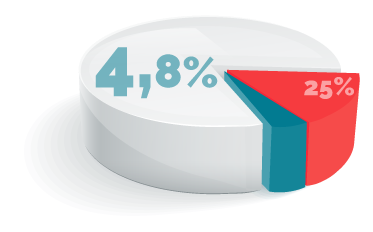

Ajuste individualizado

que prácticamente elimina las dolencias ocasionadas en pacientes con otro tipo de prótesis de rodilla.